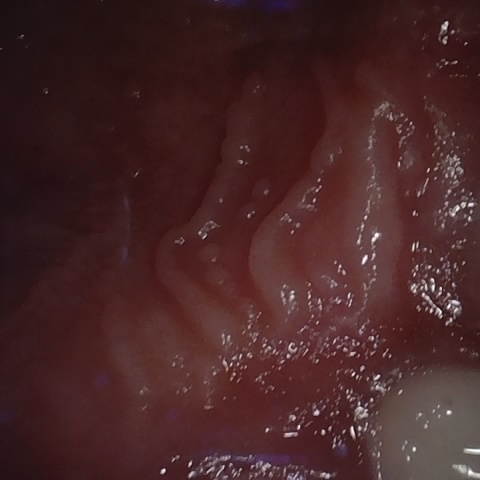

Annotated as "Good"